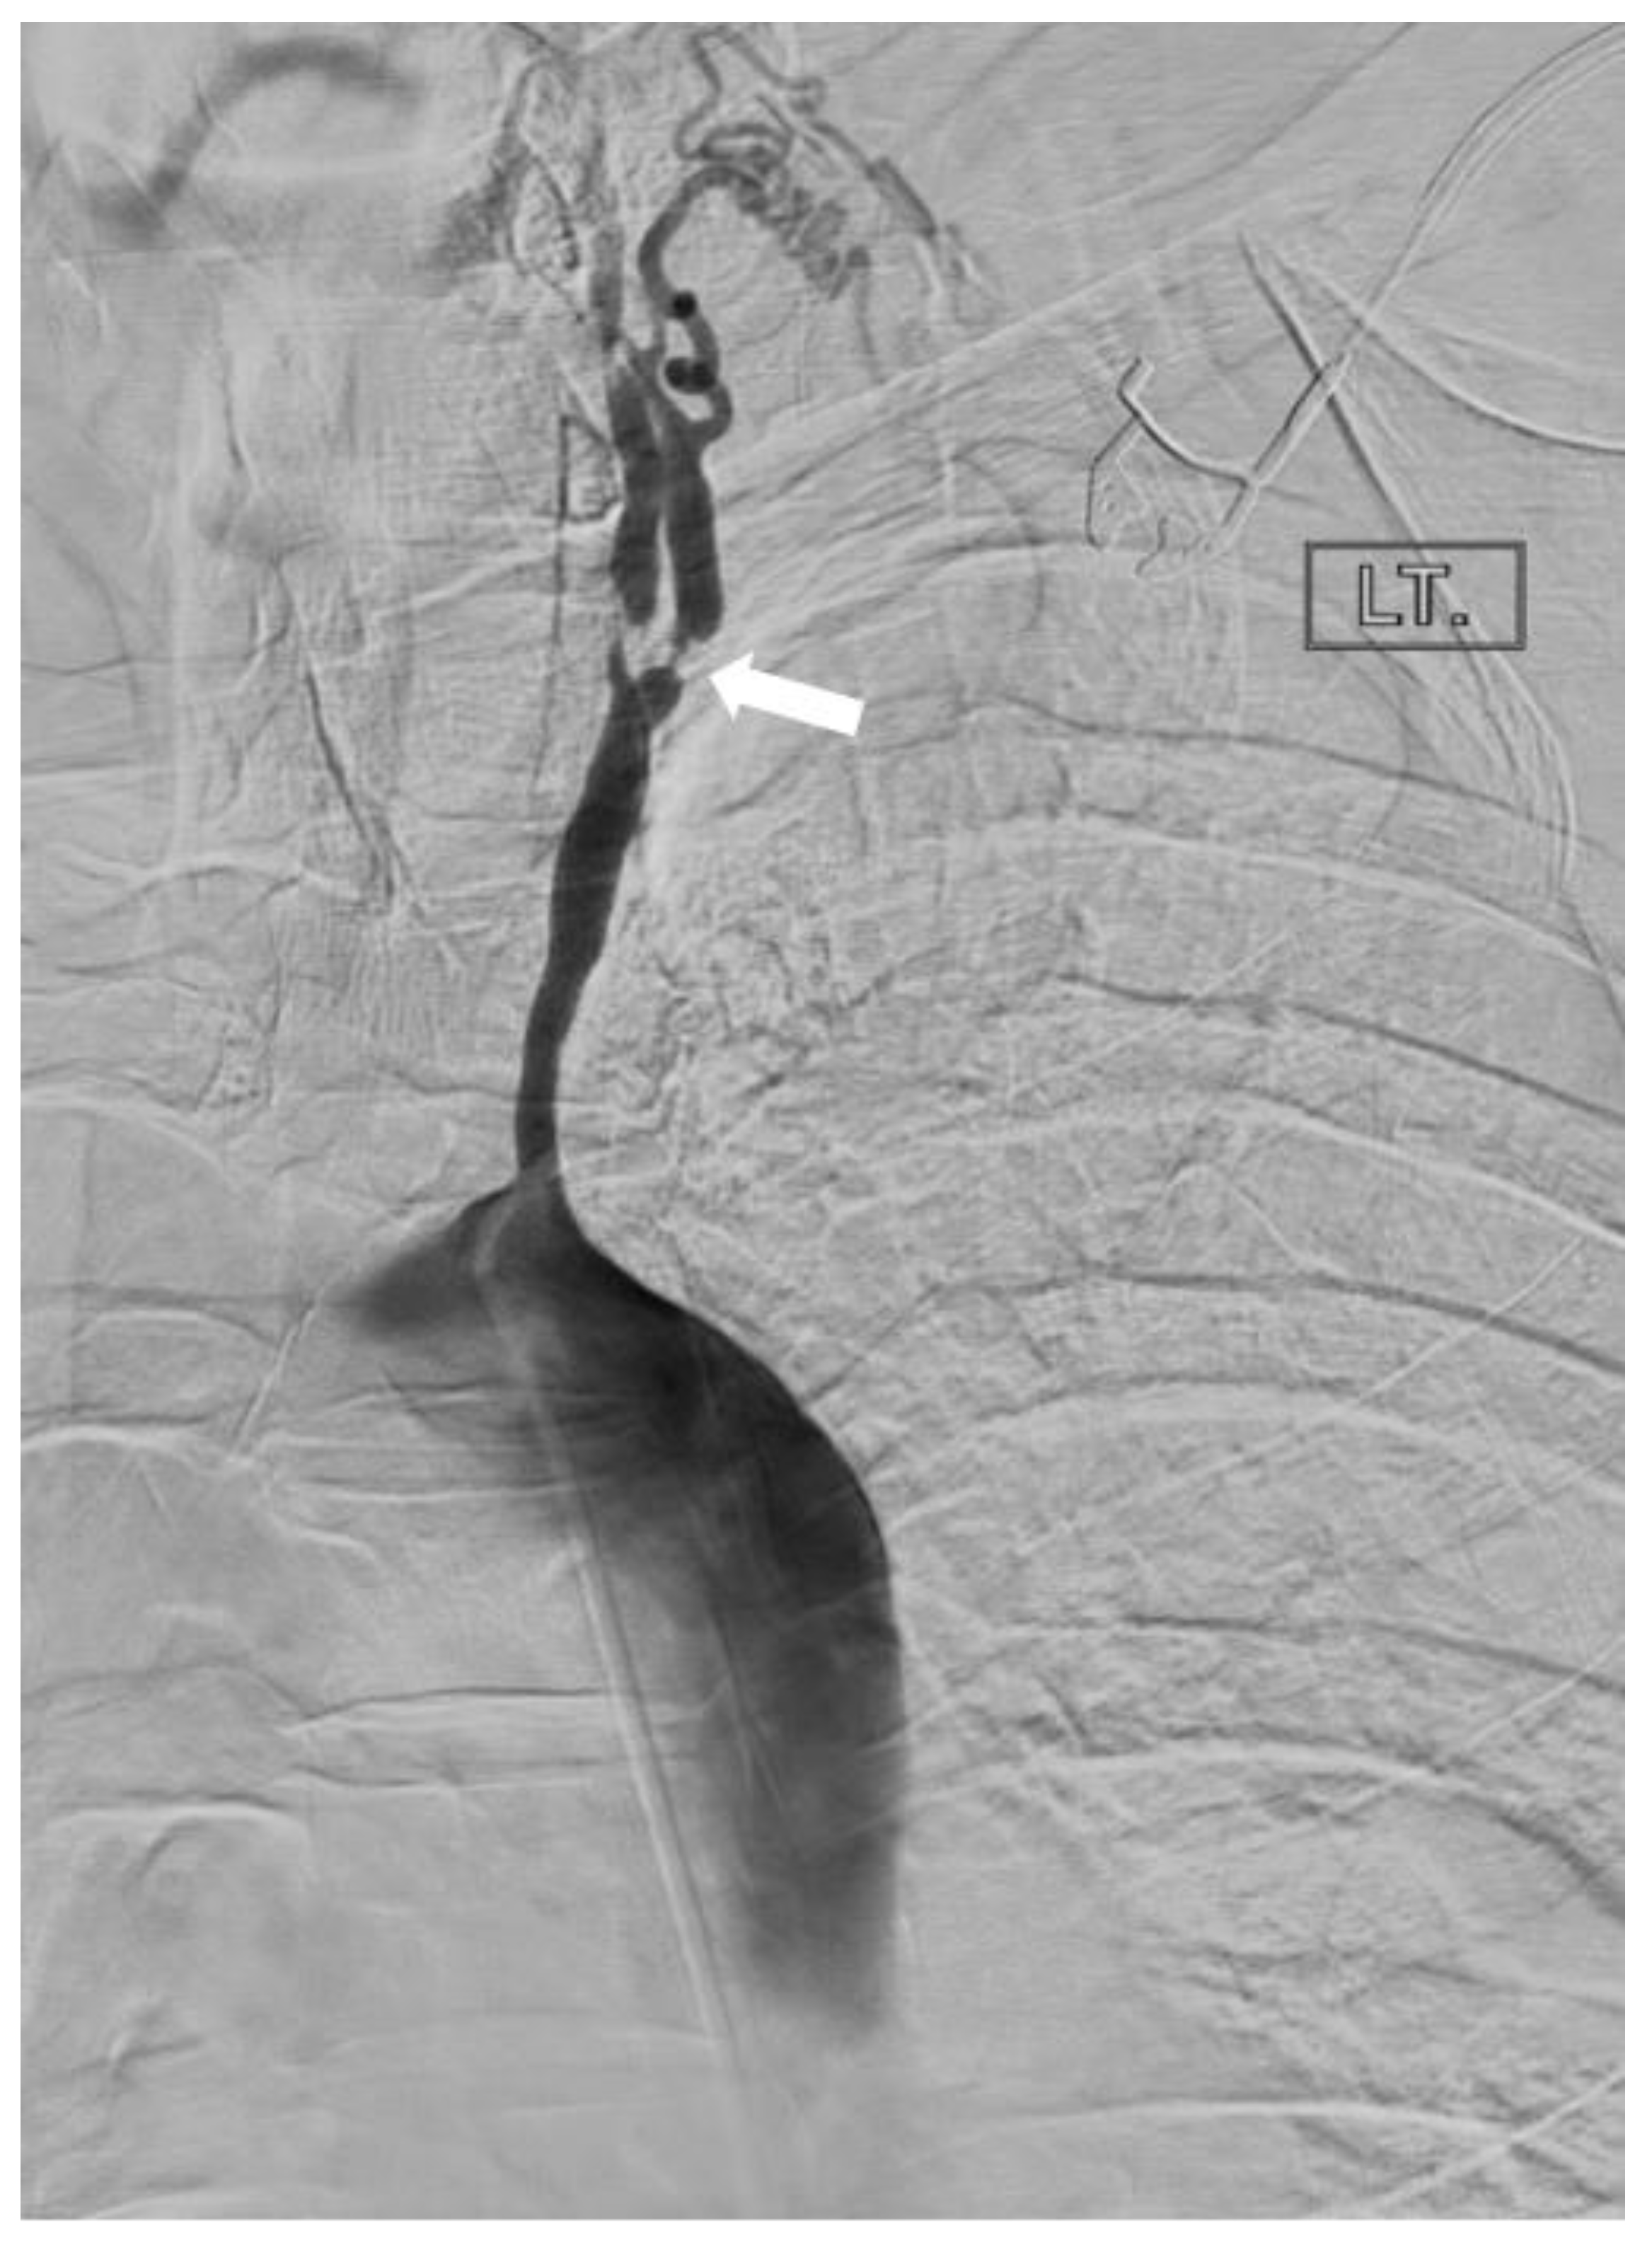

2.1.2. Takayasu’s Arteritis

- Ghembaza, M.E.A.; Boulenouar, F.; Lounici, A. “Macaroni Sign” in Takayasu Arteritis. J. Cardiovasc. Imaging 2018, 26, 186–187. [Google Scholar] [CrossRef]